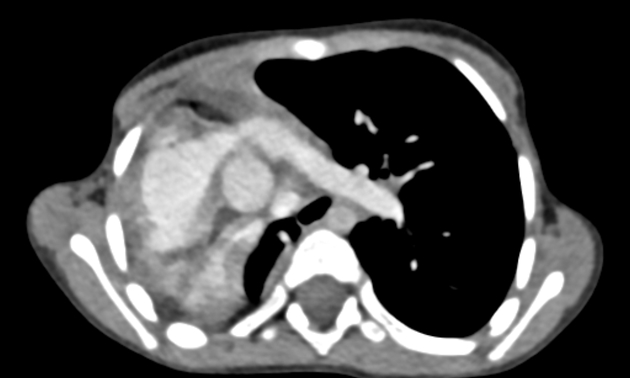

МСКТ при гипоплазии лёгких выявляет следующие анатомические признаки:

- В нативном режиме определяется уменьшение объёма одного или обоих лёгких с выраженной асимметрией грудной клетки, смещением средостения и уменьшением количества сосудистых структур в зоне поражения.

- В режиме сканирования мягких тканей визуализируются редуцированная лёгочная ткань с истончённым бронхосудистым пучком, а также компенсаторное увеличение контралатерального лёгкого и диафрагмальное возвышение.

- В режиме с контрастированием фиксируется снижение числа и диаметра сосудов в зоне гипоплазии, с нормальной васкуляризацией остальных отделов, что подтверждает врождённую редукцию лёгочного кровотока.

- В режиме высокоразрешающего сканирования лёгочной ткани выявляются недоразвитые бронхиальные структуры, отсутствие дистальных разветвлений, а также истончённые участки субплевральной зоны.

- В режиме с многоплоскостной реконструкцией уточняется степень гипоплазии, её сегментарное или долевое распространение, положение трахеобронхиального дерева и взаимодействие с крупными сосудами.

- В режиме трёхмерной реконструкции визуализируется анатомическое несоответствие объёма лёгочной ткани и грудной клетки, асимметрия сосудистого русла и структура бронхов.